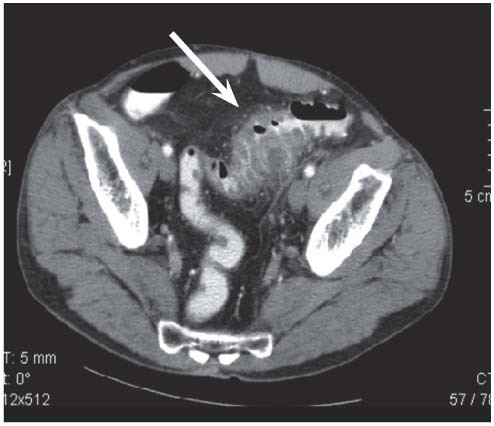

11

Q

Patient hospitalisée pour douleurs en FIG, fièvre. qu’est ce que c’est?

A

Diverticulite aiguë sigmoïdienne